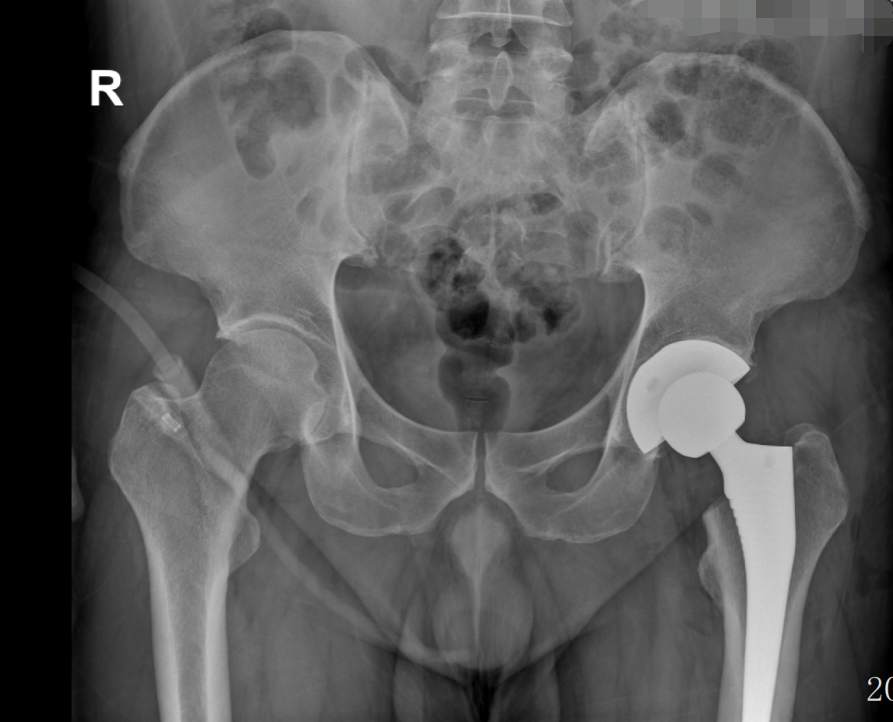

近日,我院骨科在南方医科大学第三附属医院(以下简称“南医三院”)派驻专家、学科带头人胡舒主任的带领下,为一名43岁的壮年患者吴先生(化名)实施左侧全髋关节置换术。

经胡舒主任详细检查,吴先生确诊为左侧股骨头缺血性坏死(三期)。由于保守治疗效果不佳,为有效改善功能、缓解症状,胡舒主任建议进行全髋关节置换。在充分沟通和了解了自己的疾病及治疗方式后,吴先生选择在家门口的东凤人民医院手术治疗,方便了家人护理和后续自己的定期复诊。

术前(骨盆正位)                                                                                                                           术后(骨盆正位)